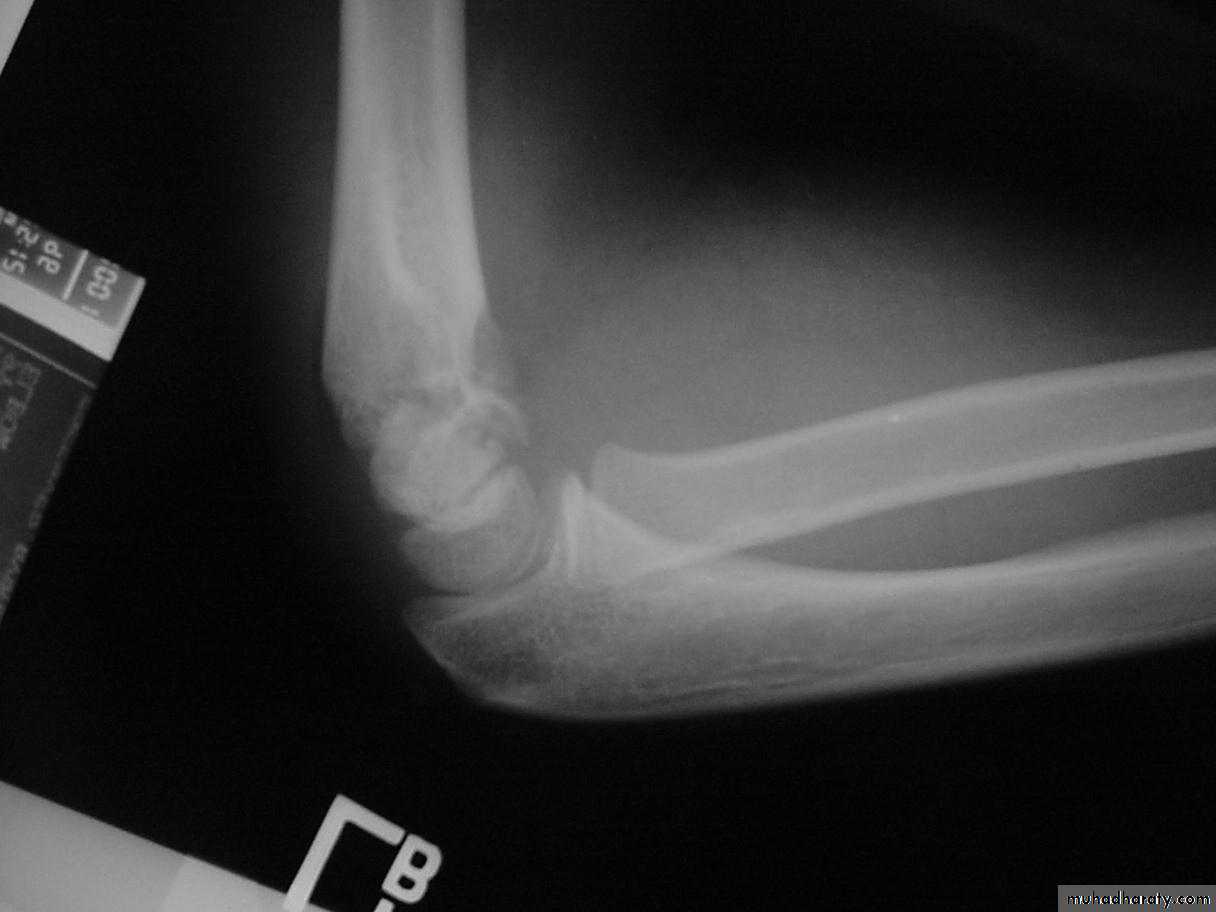

II. Mechanism of Injury

What is the mechanism of injury

for extension type supracondylar fractures ?As the

extended extremityattempts to break

the fall,

the olecranon

is forced

deep into its fossa.

This causes

the humerus to failin the weak metaphyseal

supracondylar area.